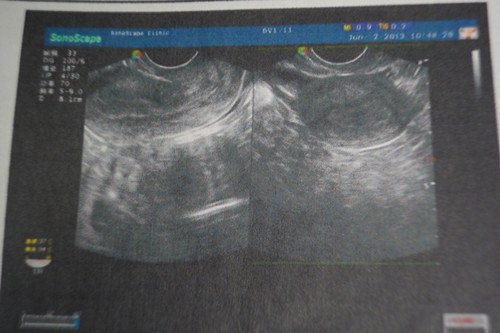

在三甲医院检查出慢性盆腔炎、细菌性阴道炎、宫颈糜烂中度,医生建议用Leep刀手术,我尚未生育

能不开刀 只用中药调理加上平时注意能治好么 望专家指点 最好能给个  中药处方。谢谢!一下是我的检查结果